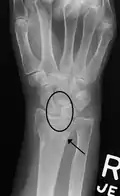

Dynamic instability: Increased scapholunate distance (between yellow lines) upon ulnar deviation of the wrist, but not otherwise. -